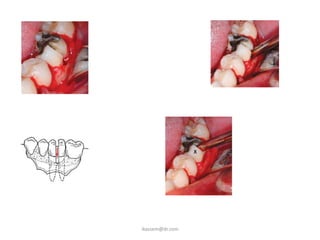

3-Fracture of the tooth

Force, technique, root anatomy

Caries

Fracture of the alveolus

• Fracture of :

-tooth being extracted

-alveolar bone

-maxillary tuberosity

-adjacent teeth

-mandible

Fracture of Alveolar Process

Fracture of the Buccal or Lingual Cortex

Cause

Inadequate exposure & excessive force

Prevention

Adequate bone removal & eposure